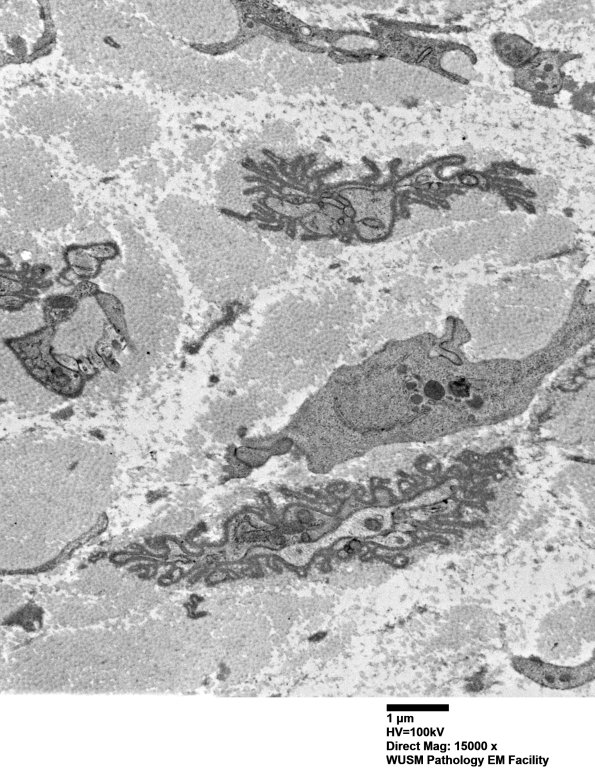

4G1,2 There are minimally preserved bands, a likely impediment to axonal regeneration.